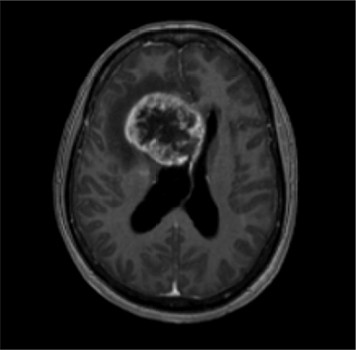

Bij neurologisch onderzoek reageert ze traag, is haar concentratievermogen verminderd en heeft ze een breed-basisch looppatroon. Een MRI-scan laat een groot ruimte-innemend proces rechts frontaal zien [figuur 1–3]. Na partiële turmorresectie wijst histologisch onderzoek uit dat het om een glioblastoom gaat.

Figuur 1 | Axiale coupe van de MRI-hersenen: we zien een grillig ruimte-innemend proces rechts frontaal met contrastaankleuring, met een omringend vasogeen oedeem, midline shift en doorgroei in de falx cerebri.

Een glioblastoom bestaat meestal uit een enkele massa die zich supratentorieel bevindt. 5 Bij beeldvormend MRI-onderzoek wordt de tumor veel beschreven als een ‘door een ring omgeven’ laesie, zoals ook in deze casus [figuur 1]. Door deze ringvorm wordt een glioblastoom soms foutief gediagnosticeerd als een abces. 9 Hooggradige gliomen hebben abnormale vaten die veel ‘lekken’ doordat de bloed-hersenbarrière abnormaal permeabel is, waardoor er op MRI-beelden meestal contrastaankleuring te zien is. Een glioblastoom kan doorgroeien naar aanliggende hersenkwabben of via de liquor. Hij metastaseert echter zelden buiten het zenuwstelsel. 5